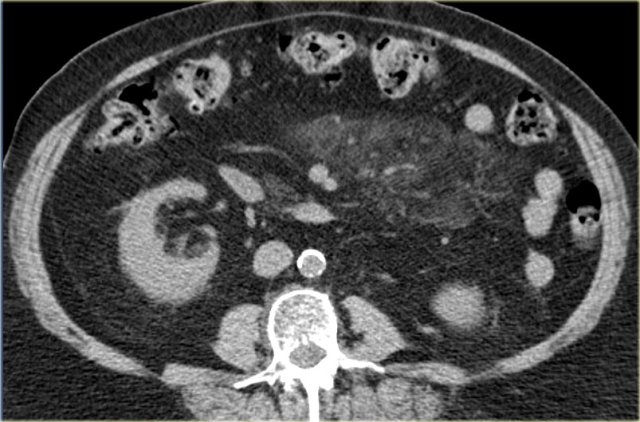

Echinococcal Cyst

It is unusual for an echinococcal cyst to be located in the peritoneum.

It favors the liver, the spleen and even the kidney over the peritoneum.

On the left we see cysts in the peritoneum and in the spleen.

Notice the daughter cysts as small dark lesions within the large peritoneal cyst (arrows).

In the pelvis additional echinococcal cysts are seen.